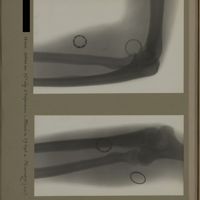

0134 - Page 22 - [Radiographies du coude et du tiers supérieur de l'avant-bras]0134 - Page 22 - [Radiographies du coude et du tiers supérieur de l'avant-bras]

0139 - Page 27 - [Radiographies du coude]0139 - Page 27 - [Radiographies du coude]

0144 - Page 32 - [Radiographies du coude]0144 - Page 32 - [Radiographies du coude]